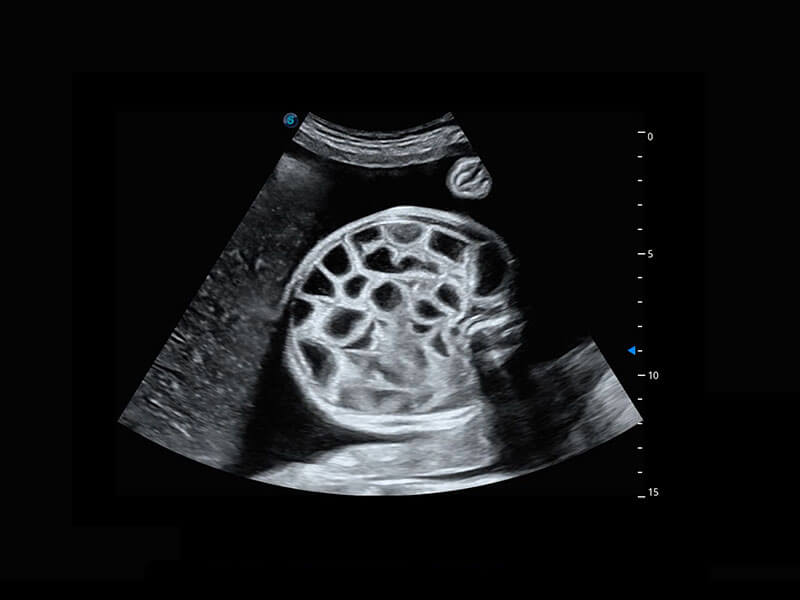

四腔切面

四腔心血流